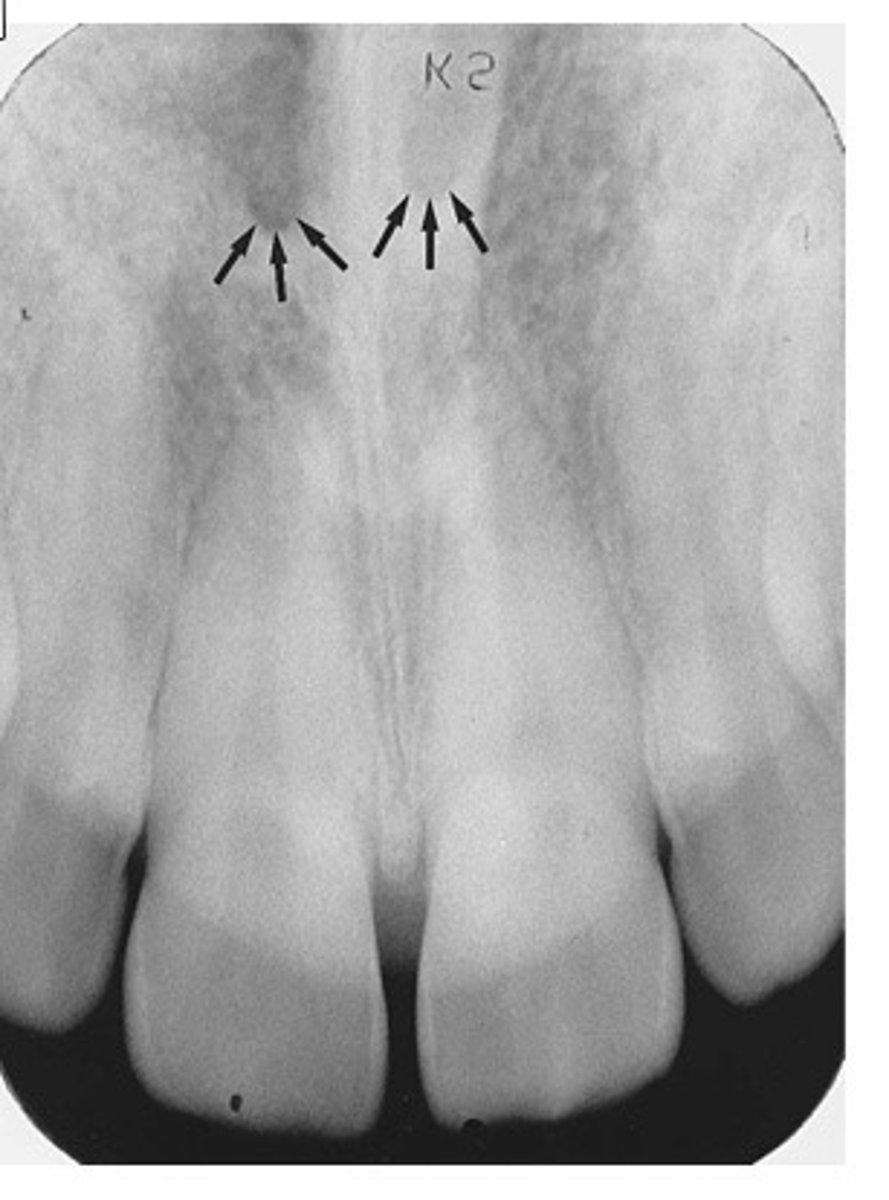

Superior foramina of the incisive canal

What is the radiolucent structure seen here?